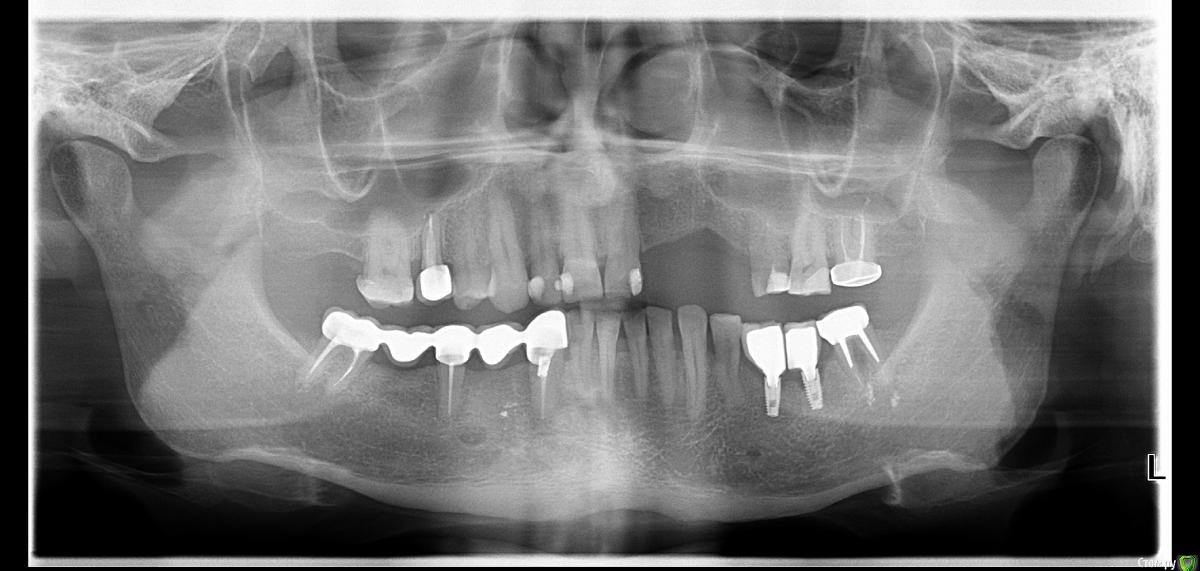

витаХА Опубликовано 23 октября, 2015 Поделиться Опубликовано 23 октября, 2015 Добрый день всем! Что то у меня всё не слава богу идёт с имплантами. То одно,то другое,а теперь вот третье.С некоторых пор начал замечать болезненность между двумя имплантами при чистке ирригатором. Временами очень ощутимую.Обратился к врачу с этим вопросом на что получил ответ пока не пользоваться ирригатором, а просто выполаскивать эти места водой после еды. По его мнению видимо ирригатор травмирует слизистую. При всём при этом при чистки этих мест ирригатором чувствуется неприятный запах из них и если я буду их просто выполаскивать водой боюсь проблема с запахом ещё больше усугубится. Уже после посещения решил сделать ортопонаграму и проконсультироваться в другом месте и здесь. Может кто что посоветует как быть. В одной клинике сказали что это забивается пища в десны вокруг имплантов и травмирует слизистую и даже вроде как уходит кость с импланта. Вердикт - переделывать всё протезирование. Выкладываю снимок в котором я не очень разбираюсь, может кто подскажет какой ни будь выход или хотя бы в каком направлении идти. Ссылка на комментарий

Паращук Роман Опубликовано 28 октября, 2015 Поделиться Опубликовано 28 октября, 2015 С первыми двумя пунктами более менее понятно.А что такое коронки с адекватным профилем появления???Если я правильно понял то протезирование выполнено неправильно???Вы рискуете потерять оба импл. в недалеком будущем. Проблема в том что было не правильно выбран абатмент и не правильно изготовлена коронка на него. На рентгенограмме желтым где кость сейчас,предположительно,красным где хотелось бы видеть,синим проблемные зоны. Как бы ситуацию вела наша команда. Снятие конструкции,с ревизией зоны имплантов. А далее от степени сложности запущенности...http://s019.radikal.ru/i604/1510/07/26929112c561.jpg 2 Ссылка на комментарий

витаХА Опубликовано 29 октября, 2015 Автор Поделиться Опубликовано 29 октября, 2015 (изменено) Вы рискуете потерять оба импл. в недалеком будущем. Проблема в том что было не правильно выбран абатмент и не правильно изготовлена коронка на него. На рентгенограмме желтым где кость сейчас,предположительно,красным где хотелось бы видеть,синим проблемные зоны. Как бы ситуацию вела наша команда. Снятие конструкции,с ревизией зоны имплантов. А далее от степени сложности запущенности... Роман,огромнейшее Вам спасибо за столь развёрнутый ответ!!!О более лучших разъяснениях я даже не мог и мечтать!!!!Теперь я смогу аргументированно объяснится с врачом и попробовать решить эту проблему в пределах этой клиники или искать другого врача.Ещё раз спасибо Роману и всем врачам,которые остались не равнодушными к моей проблеме!!!Всем удачи и процветания!!! Изменено 29 октября, 2015 пользователем витаХА Ссылка на комментарий

red_butler Опубликовано 2 ноября, 2015 Поделиться Опубликовано 2 ноября, 2015 Для того чтобы решить что дальше, нужен очный осмотр. Сохранность второго импланта под вопросом. Кроме этого требуется пластика мягких тканей и пере протезирование. Ссылка на комментарий

Larnary Опубликовано 2 ноября, 2015 Поделиться Опубликовано 2 ноября, 2015 (изменено) У меня большие сомнения,что абатменты посажены до конца. И в этом вижу первопричину. Ну а неправильно изготовленные коронки добавили проблем сверху. Соавните со снимком,где формирователи Изменено 2 ноября, 2015 пользователем Larnary 2 1 Ссылка на комментарий